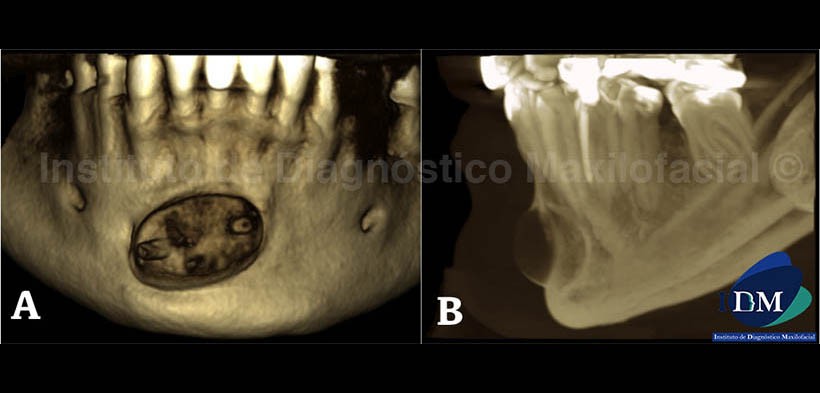

En las vistas tridimensionales (Fig. 5) se observa el lecho quirúrgico de bordes lisos y perfectamente delimitado (A), así mismo en la proyección de máxima intensidad se aprecia la neoformación ósea recubriendo el implante aloplástico (B); y por ultimo, con el filtro radiográfico (Fig. 6) ilustramos el implante de color verde para el mejor entendimiento de su posición y ubicación con respecto a la zona anterior del maxilar inferior.